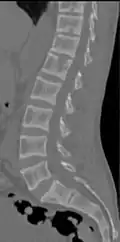

X-ray of a subtle "rugger jersey spine" due to sclerotic bands adjacent to the vertebral endplates.[18] -

CT scan of the same case.[18]